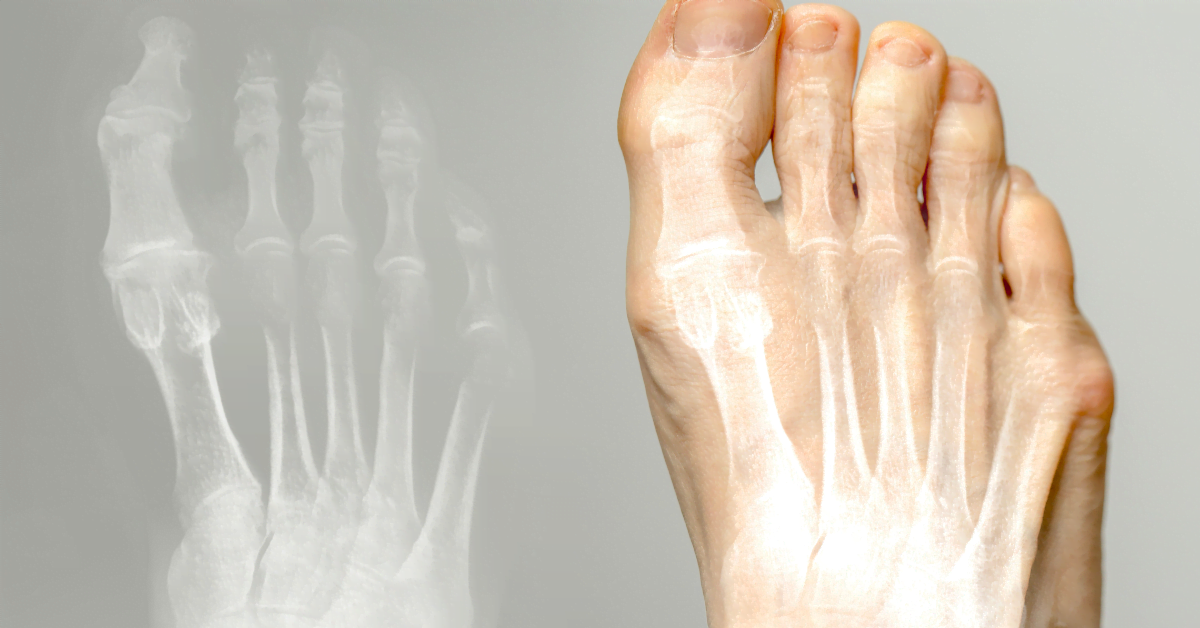

Hallux valgus (juanete) es una afección en la que el dedo gordo del pie se inclina hacia adentro y forma un bulto en la base. Puede causar dolor y molestias. Aquí lees causas, tratamiento y prevención.

El dedo gordo se dobla hacia los otros dedos, formando un bulto en el pie. Causas: zapatos estrechos, tacones altos, herencia, pies planos o artritis. El calzado inadecuado causa presión y fricción, lo que puede provocar bursitis.

El hallux valgus es una desviación del dedo gordo del pie hacia adentro, con un bulto en la base. A menudo causado por zapatos estrechos, tacones altos o herencia. Puede causar dolor y bursitis.